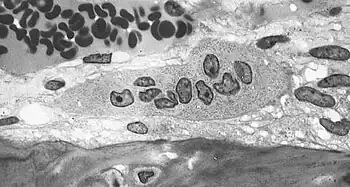

Collagen fibers of woven bone Osteoclast displaying many nuclei within its "foamy" cytoplasm.

Osteoclast displaying many nuclei within its "foamy" cytoplasm. Light micrograph of decalcified cancellous bone displaying osteoblasts forming new bone tissue, containing two osteocytes, within a resorption pit.

Light micrograph of decalcified cancellous bone displaying osteoblasts forming new bone tissue, containing two osteocytes, within a resorption pit.